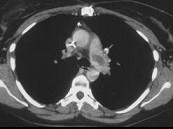

女,51岁,心脏手术后,突感胸痛,结合CT图像,最可能的诊断是 ( )A、肺癌B、肺不张C、支气管扩张D、肺水肿E、肺栓塞

问题 女,51岁,心脏手术后,突感胸痛,结合CT图像,最可能的诊断是 ( )

选项 A、肺癌 B、肺不张 C、支气管扩张 D、肺水肿 E、肺栓塞

答案 E